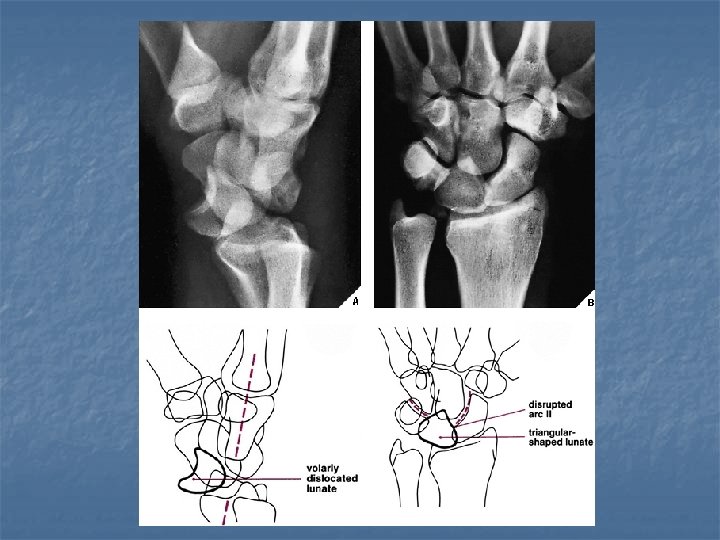

Lunate dislocation n On lateral view Axis of lunate is titled away from the articular surface of radius (spilled tea cup sign) n Capitate remains in normal alignment with radius and 3 rd metacarpal n n On dorsovolar view n Disruption of arc II while arc III remains intact

Normal anatomical relations n Dorsovolar view with wrist in neutral postion: 3 smooth unbroken arcs should be seen (Gilula arcs) Arc I: proximal articular surfaces of the scaphoid, lunate, & triquetrum n Arc II: distal concavities of scaphoid, lunate, & triquetrum n Arc III: proximal convexities of capitate & hamate n